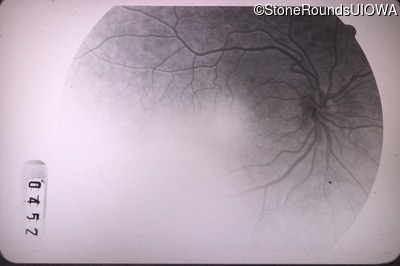

Fluorescein Angiography - Right - 20/40

Exemplar